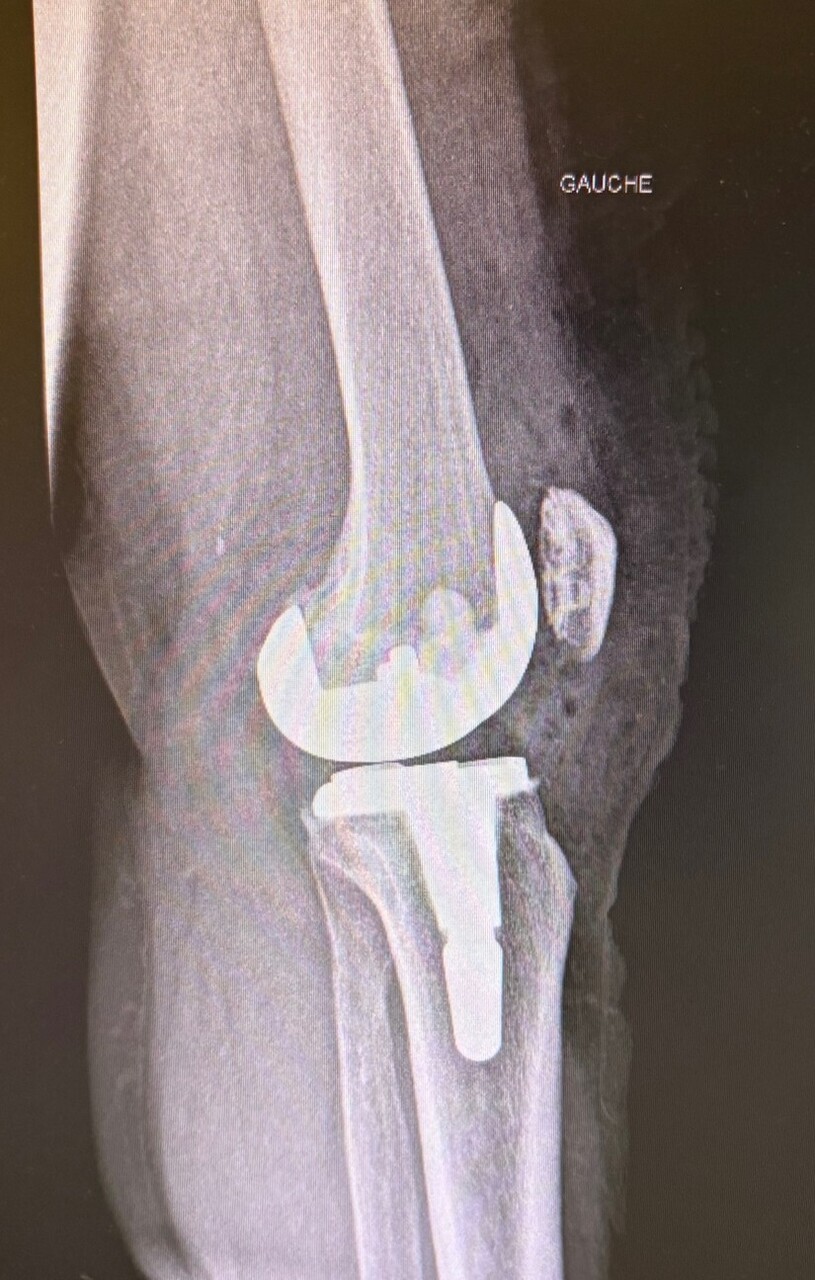

• les interventions prothétiques non conservatrices (fig. 1).

Les causes sont variables : hématome, ­lésion des parties molles, infection débutante, démontage de l’ostéosynthèse, ­luxation ou fracture périprothétique (fig. 4). Un avis chirurgical urgent doit être sollicité, parfois précédé d’un bilan d’imagerie radiologique simple et d’un ­bilan biologique (hémogramme, protéine C réactive [CRP]).

Insatisfaction du patient en postopératoire

Le médecin traitant peut être interrogé sur un résultat jugé insuffisant par le patient, après (ou non) avis du chirurgien. Cette situation n’est pas rare, notamment après prothèse articulaire : 2 % environ pour les prothèses de hanche et jusqu’à 20 % pour les prothèses de genou. Les plaintes sont variables et parfois associées (douleurs persistantes, mobilité incomplète, gênes fonctionnelles ou sportives). Le médecin peut se trouver alors en position délicate entre son patient et le chirurgien. Il est important de reprendre les échanges de courrier, notamment l’examen et l’information préopératoire. Les suites chirurgicales peuvent également expliquer ces diffi­cultés. Le résultat fonctionnel complet s’obtient généralement après six mois pour une pose de prothèse de hanche et un an après la pose d’une prothèse de genou, et certains dysfonctionnements sont de diagnostic difficile. Le plus souvent, des explications répétées suffisent. ­Toutefois, dans certains cas, un second avis chirurgical peut être pertinent. En revanche, il convient d’éviter la pres­cription de bilans d’imagerie, parfois inappropriés, comme une scintigraphie précoce moins d’un an après la pose de prothèse. En effet, des images ambiguës et non spécifiques peuvent orienter vers un diag­nostic erroné et favoriser l’évolution vers un conflit médico-légal.

Surveillance et durée de vie d’une prothèse

Une dégradation fonctionnelle tardive peut traduire une évolution de la pathologie initiale ou la dégradation du traitement (descellement de prothèse, arthrose après ligamentoplastie…). Si une prothèse est présente, même en cas de pathologie de voisinage, comme une cruralgie, un bilan radiologique de l’implant doit être effectué.

Les prothèses articulaires doivent être revues à intervalles réguliers car elles peuvent montrer des signes d’usure et/ou un descellement, initialement révélé par des radiographies et conduisant, en l’absence de signes cliniques, à une surveillance plus rapprochée. En cas de signes cliniques et selon l’état général, le changement de prothèse est souvent possible, avec une morbidité actuelle moindre.

La durée de vie d’une prothèse ne peut pas être prédite individuellement. Mais hors complications (infections, fracture…), elle est en moyenne de vingt ans. Cette durée varie en fonction de l’indication initiale, des antécédents locaux et généraux et de l’activité du patient.